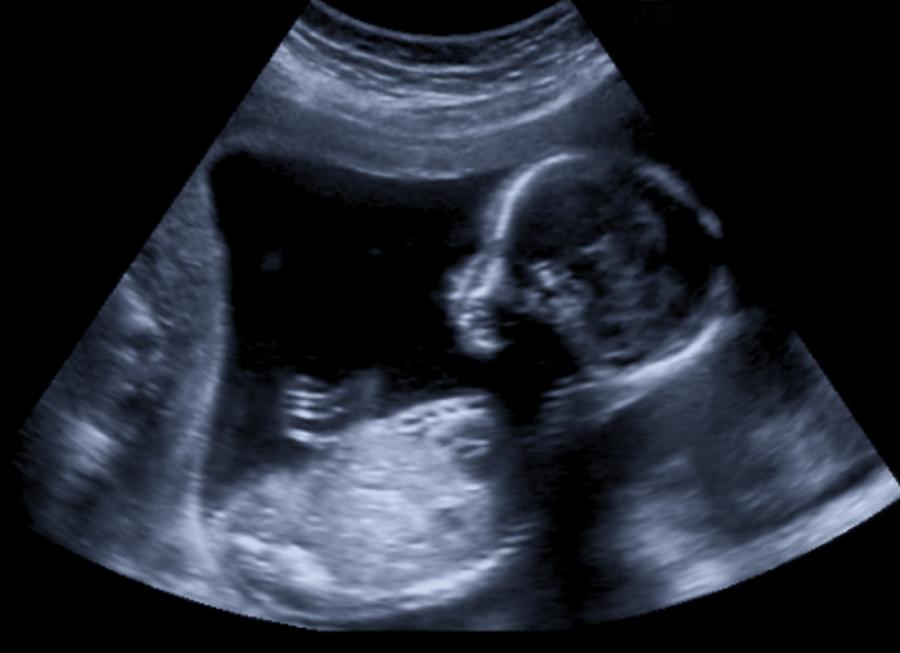

Първоначално Арифа Султана ражда син в края на февруари, но 26 дни по-късно влиза отново в болница, тъй като изпитва остри болки в корема. Именно тогава ражда още две бебета – близнаци.

Феноменът е познат на науката. Той е известен като двойна матка и не толкова рядко явление, колкото вероятно предполагате. Една от причините да не се знае за необикновеното й състояние е, че момичето е от бедно семейство и не е ходила на лекар през цялото време на бременността си.